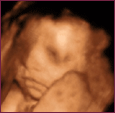

УЗД від 28 до 30 тижня

У цей час дитина має повні щоки, оскільки жир під шкірою дитини формуються більш швидко.

| 28 тиждень | 28 тиждень | 28 тиждень |